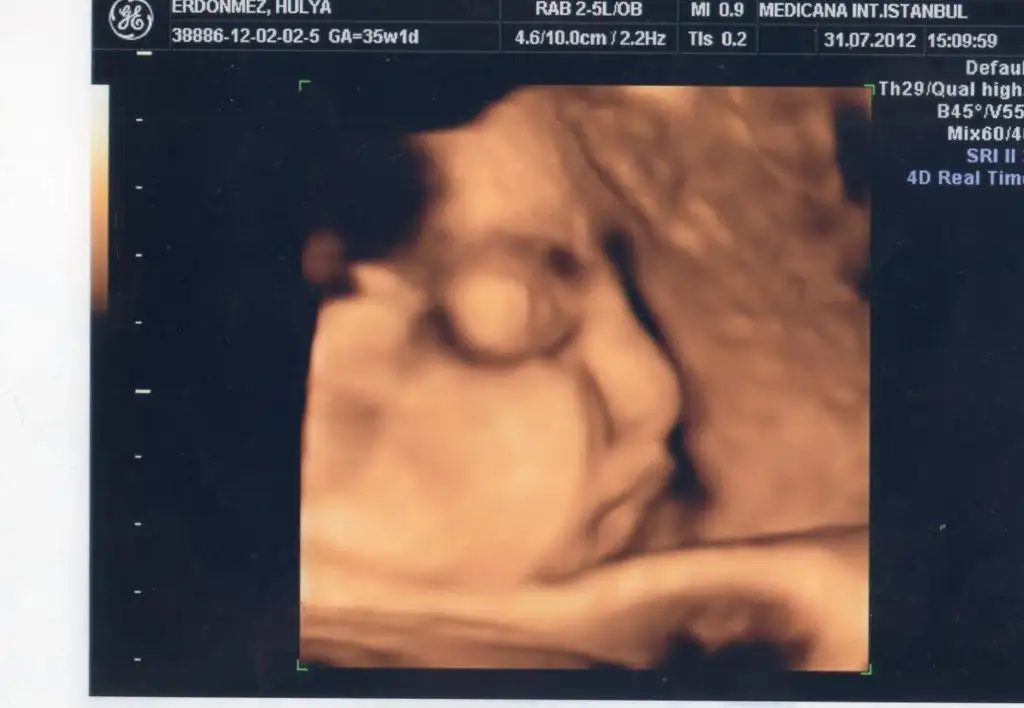

Ay ne güzel banada gönder bizde marketler uzak taşımakta zor karpuzu kavun alıyoruz hep :)) yesinler oğluşunu senin.. benimkinin geçen gördük suratını çok tuhaf oluyor insan astım resimlerini buzdolabına gidip gelip seviyorumbir dahaki kontrol haftaya perşembe bakalım ne dicek doktr böbrek genişlemesi var demişti bebişim için inşaallah geçmiştir önemli bişey değildir :18: